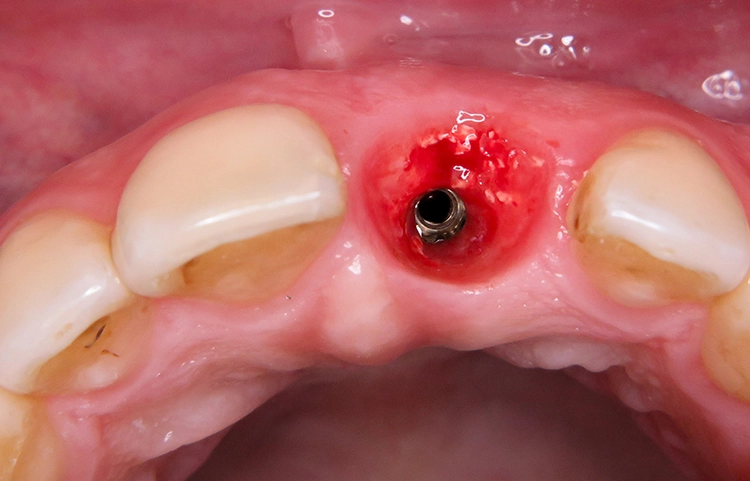

Unter Lokalanästhesie wurde der beherdete Zahn 21 extrahiert und hierbei auf die maximale Schonung der vestibulären Lamelle geachtet. Die Entzündung konnte rückstandslos entfernt werden. Die Sondierung ergab eine intakte faziale Knochenlamelle (Abb. 6). Die frische Extraktionsalveole wurde als Implantatbett aufbereitet und das Implantat (BLX ø 4 mm, 14 mm) entsprechend der Planung dreidimensional im palatinalen Bereich der Alveole inseriert [3,6] (Abb. 7 und 8).